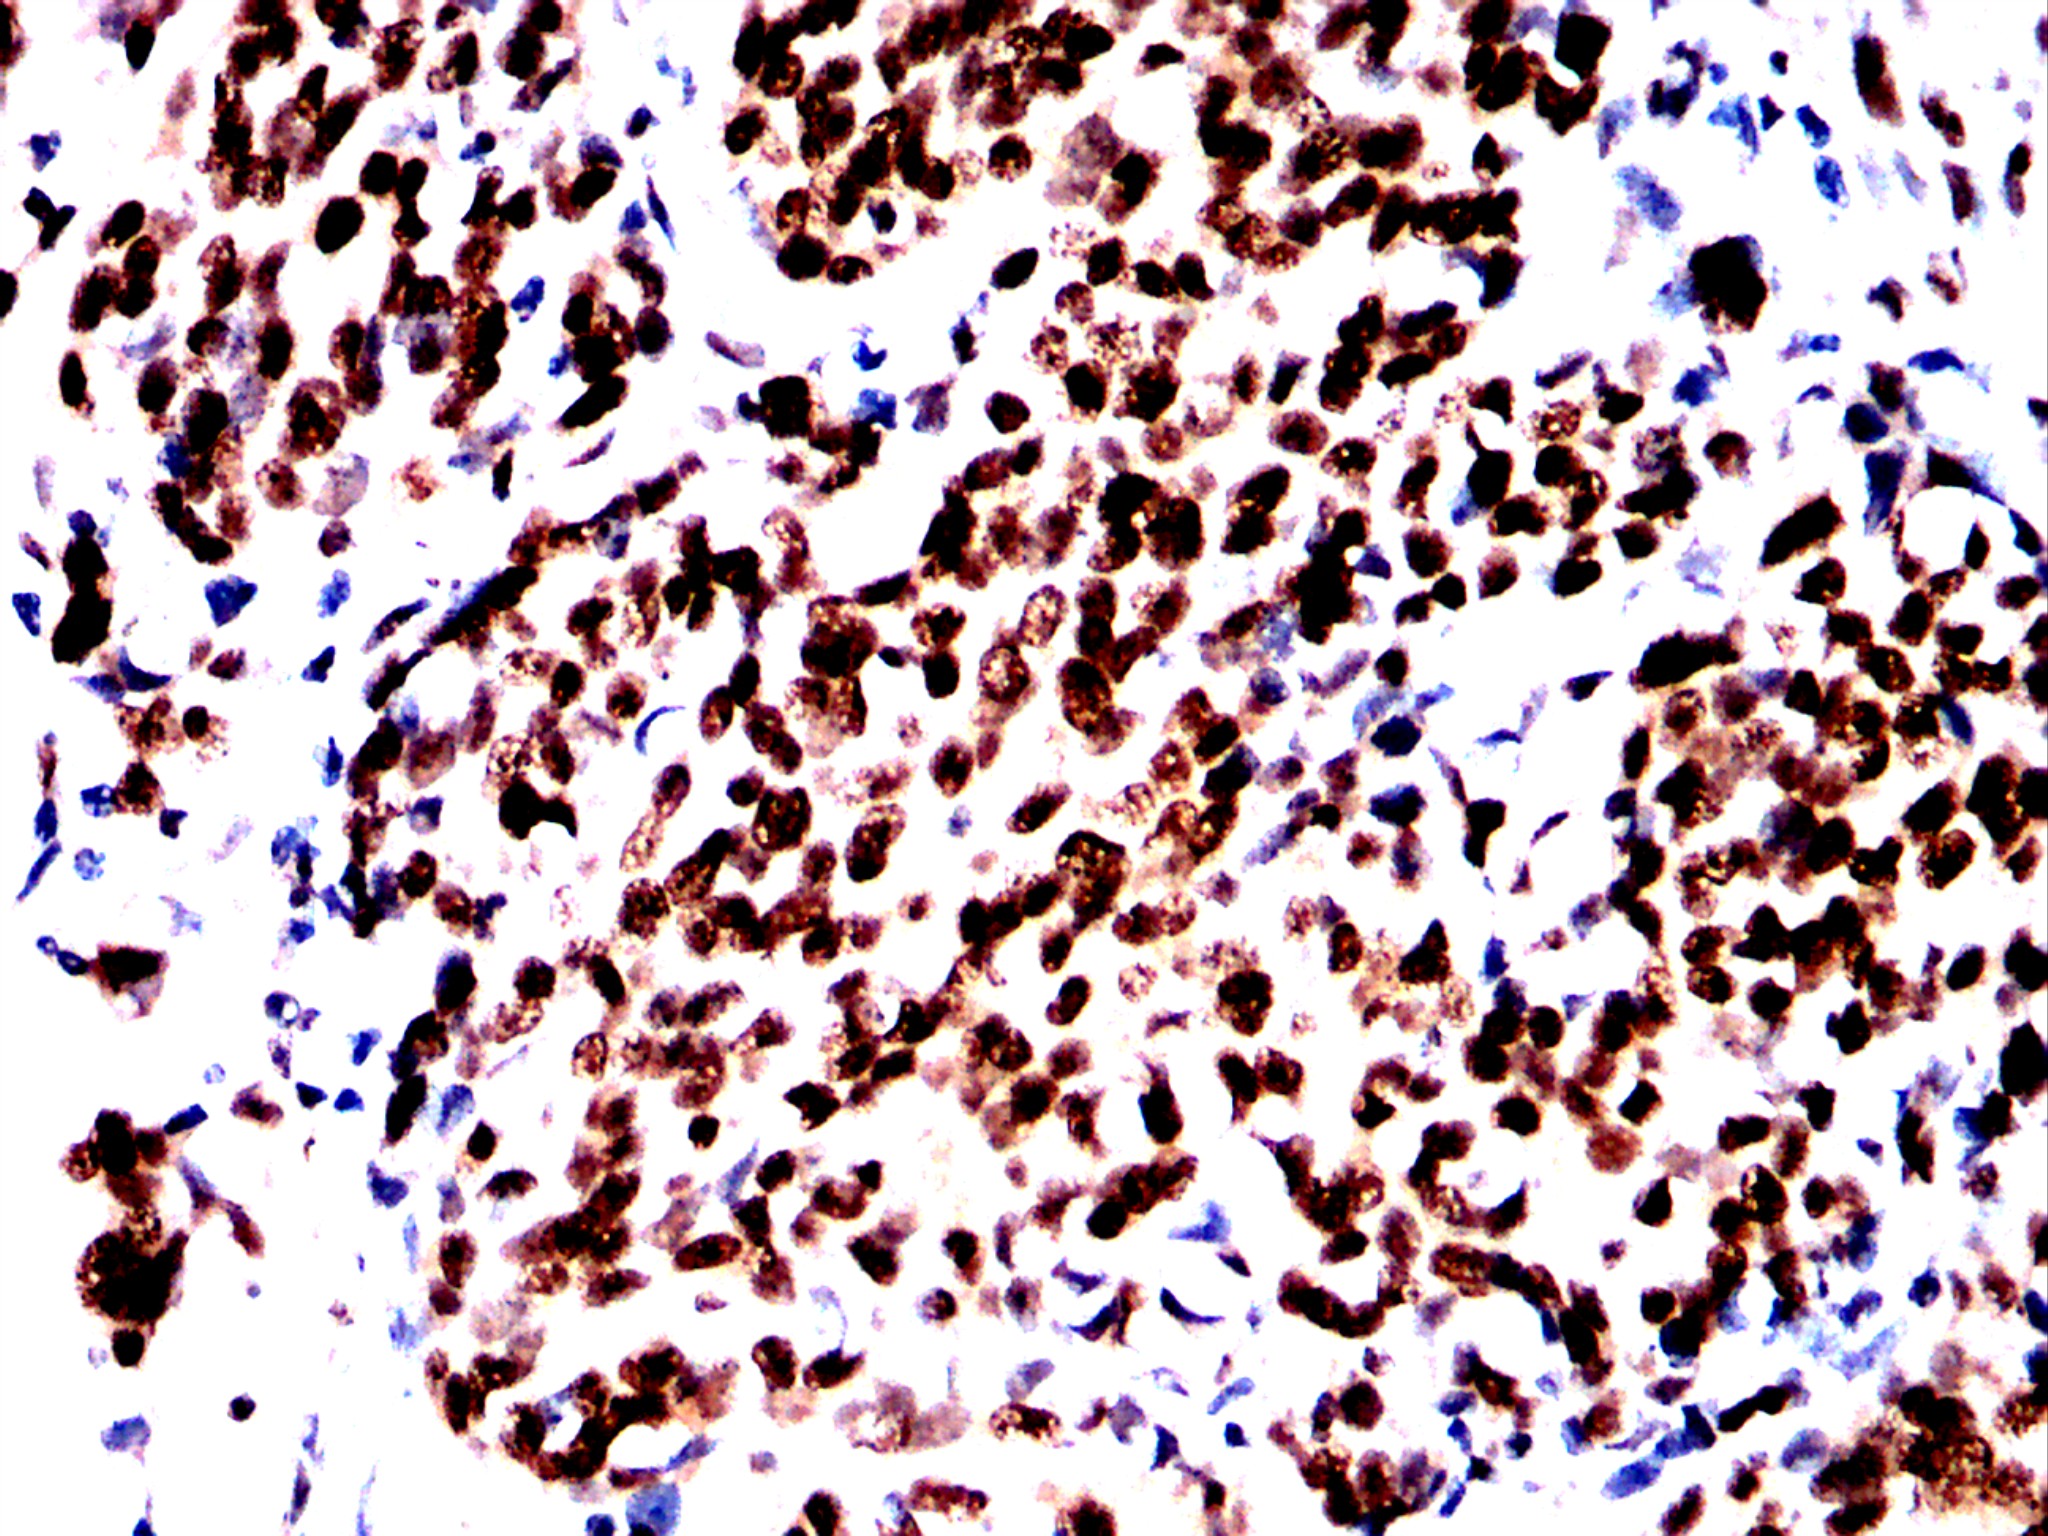

Immunohistochemical analysis of paraffin-embedded breast cancer tissues using MDM2 antibody with DAB staining. Pre-treat the sections with heat-mediated antigen retrieval using sodium citrate buffer (pH 6.0) (OM750020) for 2 minutes. Wash the sections with ddH₂O and PBS (OM750003). Block the tissue with 10% non-immune goat serum(OM760028) at room temperature for 30 minutes. Incubate the tissue with the primary antibody diluted at a ratio of 1:1500 at 4°C overnight. At room temperature, dilute the secondary antibody, Goat Anti-Rabbit IgG(H&L)-HRP (OM644332), at a ratio of 1:200 and incubate for one hour. Use DAB(OM760029)as the chromogenic agent. Counterstain the tissue with hematoxylin, and mount the tissue sections with neutral gum.IHC

Immunohistochemical analysis of paraffin-embedded breast cancer tissues using MDM2 antibody with DAB staining. Pre-treat the sections with heat-mediated antigen retrieval using sodium citrate buffer (pH 6.0) (OM750020) for 2 minutes. Wash the sections with ddH₂O and PBS (OM750003). Block the tissue with 10% non-immune goat serum(OM760028) at room temperature for 30 minutes. Incubate the tissue with the primary antibody diluted at a ratio of 1:1500 at 4°C overnight. At room temperature, dilute the secondary antibody, Goat Anti-Rabbit IgG(H&L)-HRP (OM644332), at a ratio of 1:200 and incubate for one hour. Use DAB(OM760029)as the chromogenic agent. Counterstain the tissue with hematoxylin, and mount the tissue sections with neutral gum.